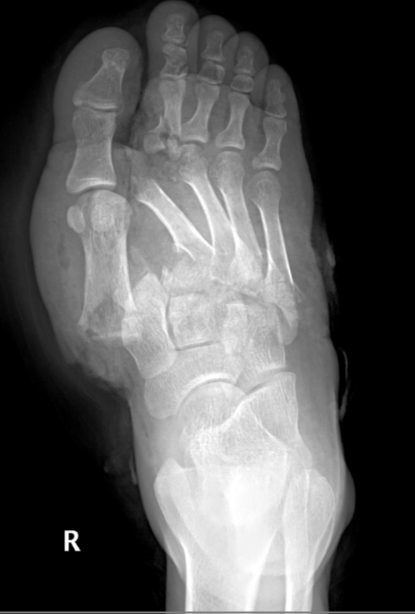

• Divergent - basically 1st digit moves medially and all other digits move laterally (increase space between 1st and second digits) (3rd picture)

• Case courtesy of Ankit Balani, Radiopaedia.org, rID: 34177 (divergent lisfranc injury)